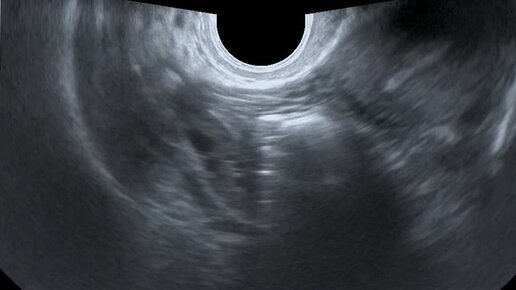

Видео: Поперечное сканирование матки. Правый яичник расположен на расстоянии от угла матки

Ультразвуковые находки от врача УЗД Зорина Я.П.